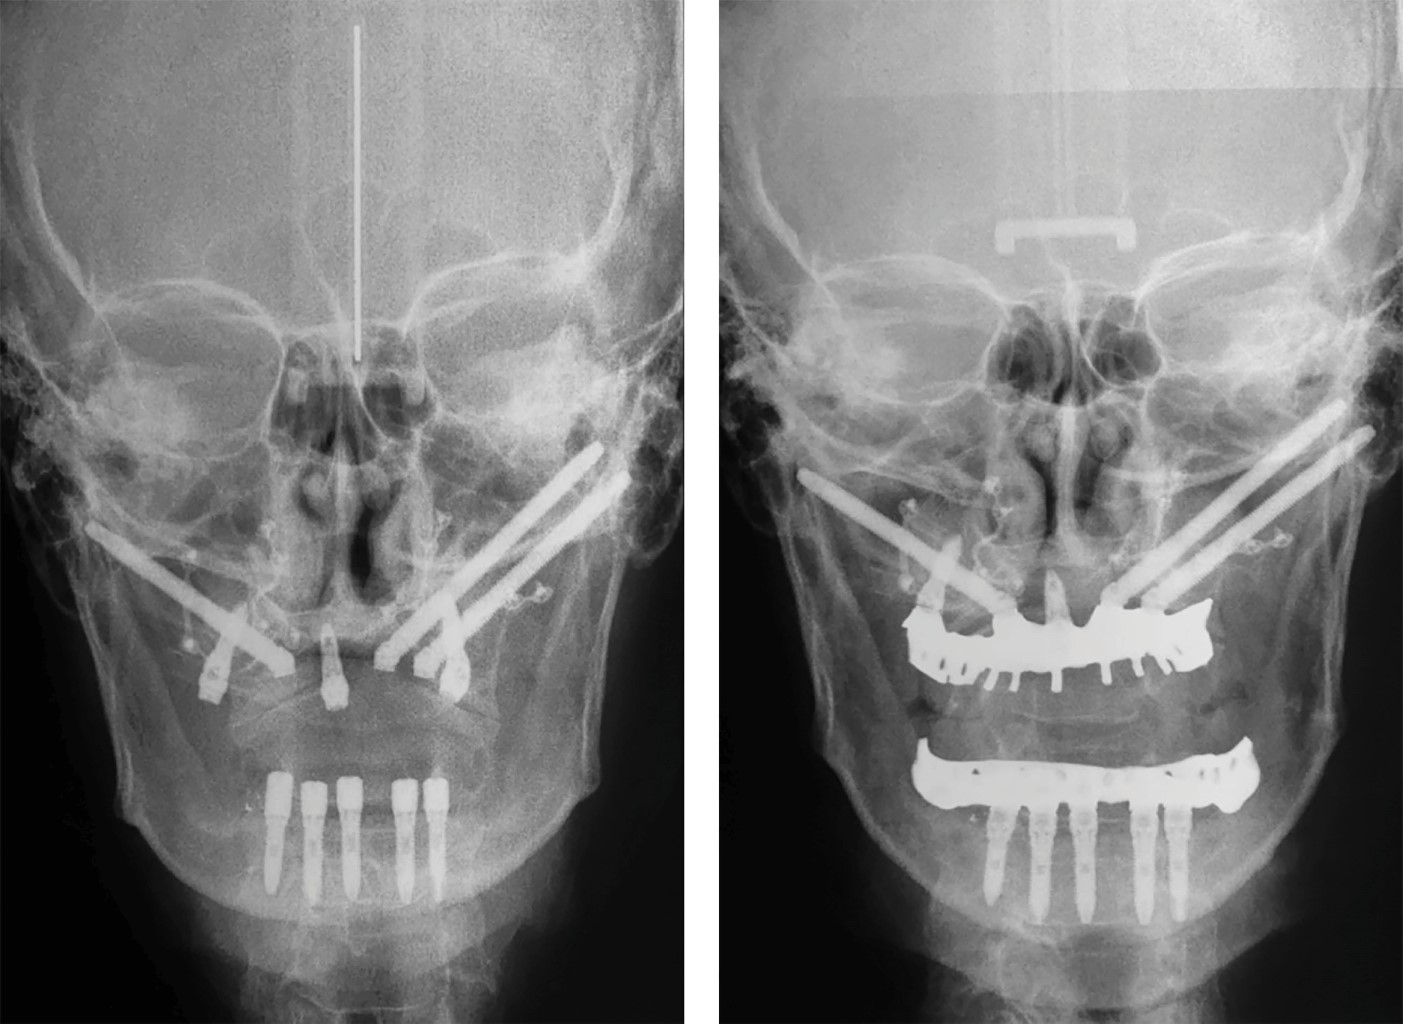

PLANIFICACIÓN QUIRÚRGICA

La planificación preoperatoria se realizó en cinco casos procesando los archivos DICOM (comunicaciones digitales de imágenes médicas) de las tomografías computarizadas obtenidas mediante el tomógrafo NewTom 5G, a través del software Mimmics Innovation Suite v6 con el apoyo del ingeniero biomédico. La osteotomía Le Fort I del maxilar atrófico, la inserción de implantes dentales/zigomáticos y la rehabilitación protésica se simularon en los modelos virtuales 3D utilizando archivos de lenguaje de triángulos estándar (STL) para impresión 3D. Después de la validación final, se fabricaron guías de corte quirúrgicas específicas del paciente en titanio utilizando la impresora Renishaw AM400 (manufactura aditiva por fusión de polvo de titanio con haz de láser), plantillas de guía de perforación de implantes y placas de osteosíntesis personalizadas (Figura 3). Un sólo caso fue tratado de forma análoga.

• 2. Osteotomías maxilares mediante la utilización de guías quirúrgicas personalizadas para realizar cortes precisos en el hueso maxilar (Figura 4).